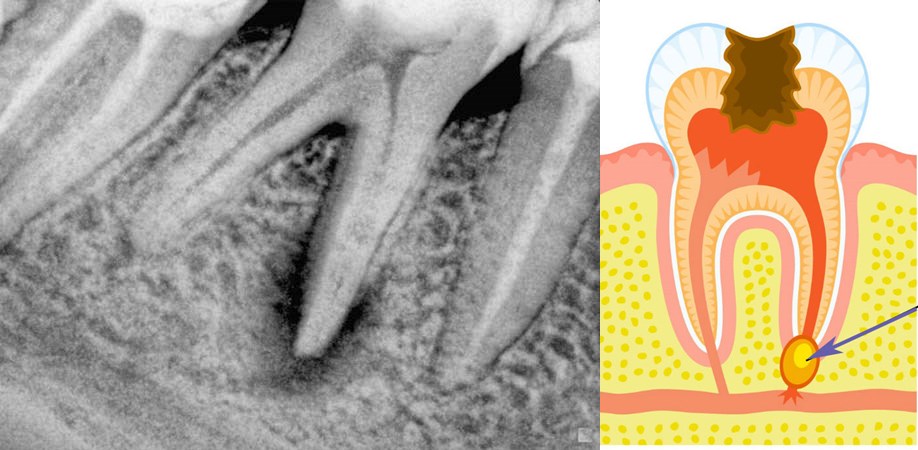

При длительном течении процесса околоверхушечная костная ткань постепенно разрушается, образующийся дефект замещается грануляционной тканью.

В одних случаях у больного вокруг грануляционной ткани образуется плотная фиброзная капсула — зубная гранулема, которая со временем может превратиться в кисту, заполненную гноем и продуктами воспаления.

Болезнь чаще возникает при длительно протекающем кариесе, либо после его лечения, если в ходе процедуры стоматолог не полностью устранил очаг инфекции. Эту форму называют апикальной или верхушечной. Маргинальным или краевый периодонтит способен развиваться из-за травматического повреждения десны и внесения инфекции.

- Фиброзная форма хронического периодонтита является начальной и практически незаметна — боли носят несистематический характер, или полностью отсутствуют, и определить наличие воспалительного процесса можно только при помощи рентгеновского снимка.

- Гранулематозная — серьезней всех остальных. При эволюции заболевания до этой стадии в мягких тканях образуются гранулемы — дёсенные пустоты, которые заполнены гноем, представляющим собой идеальную среду для жизни микробов. Они фактически представляют собой мину замедленного действия, и удаляются только хирургическим путем.